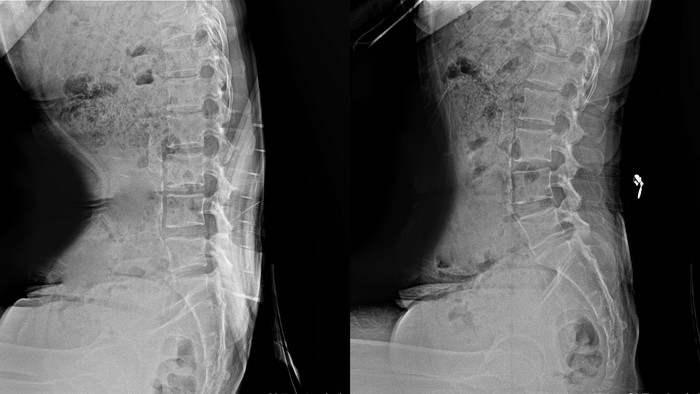

| ▲보통 의자에 앉은 자세(좌)와 자생 맞춤미학 허리쿠션을 착용하고 앉은 자세(우)를 비교한 엑스레이(X-ray) 사진 |

자생 맞춤미학 허리쿠션 착용시 요추(허리뼈)가 신장되고 척추의 S자형 만곡이 유지되는 것을 확인할 수 있다.